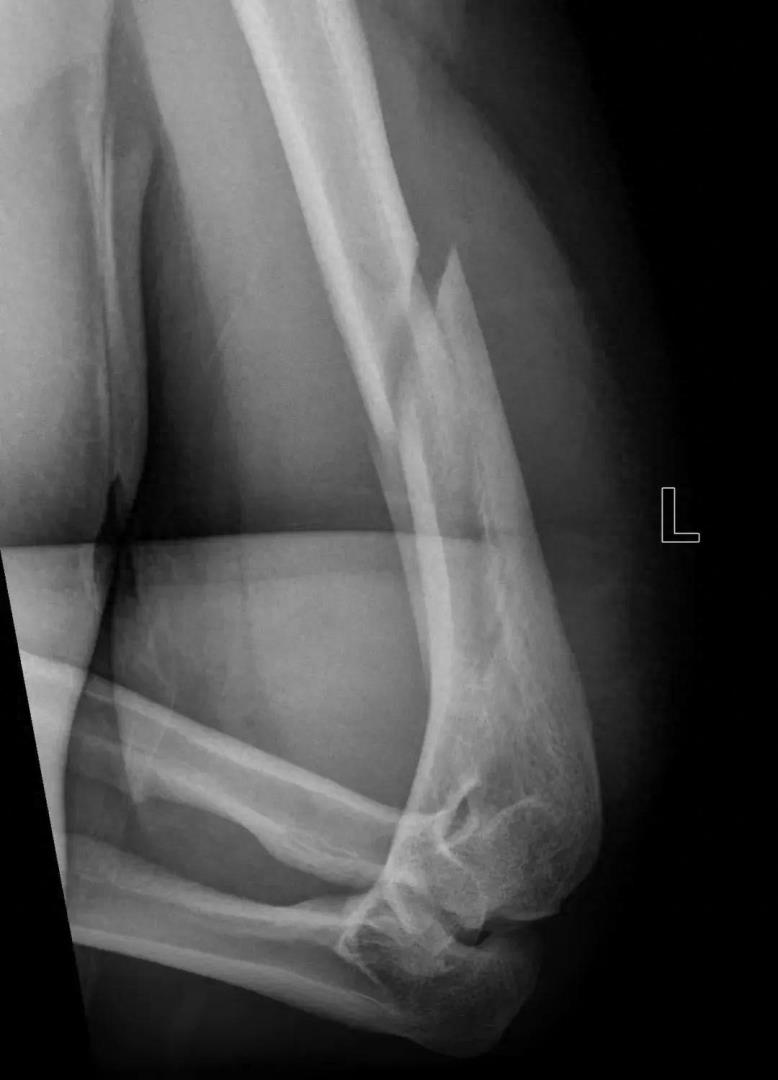

最近市人民医院创伤骨科来了一位左肱骨干骨折的病人小潘,询问病史时,小潘和他的朋友相视苦笑,原来小潘与他的朋友约起来游戏——掰手腕,他们因为两人实力相当,力气、腕力也都不相上下,双方僵持不下,手臂一直持续发力,突然听见咔嚓一声,手臂当时就动不了而且疼痛剧烈,紧接着就来医院就诊了。

CR

经过影像检查,小潘是左侧肱骨干骨折,主管医生说先左上臂夹板固定后再行手术。在完善术前检查后,小潘如期进行左肱骨骨折切开复位钢板螺钉内固定术,住院期间给予对症治疗后,现手术创口愈合良好,拆线后出院了。出院那天小潘说:“掰手腕这个事情,以后不约!”

掰手腕可以导致多种骨关节损伤,包括肱骨干骨折、肱骨内上髁撕脱骨折等,但其中最常见的还是肱骨干骨折。人的上臂就一根典型的长骨叫肱骨,在肱骨靠近肘关节上方3~4cm内,有一个圆柱形和不规则扁平骨的结合点,最为薄弱的,这个地方医学上叫肱骨髁。扳手腕的过程中,对手会通过比赛者的前臂施加给肱骨远端一个外旋应力,比赛者本人在对抗过程中通过自身的内旋肌群向肱骨近端施加强大的内旋应力,巨大的扭转应力在肱骨最薄弱处释放,造成肱骨干骨折。如果掰手腕的两个人实力差距很大,倒不容易掰断手,反而是当对抗双方势均力敌,僵持不下时,容易发生骨折。若发生骨折一定要及时就医,切不可自行处理,以避免进一步的神经损害。